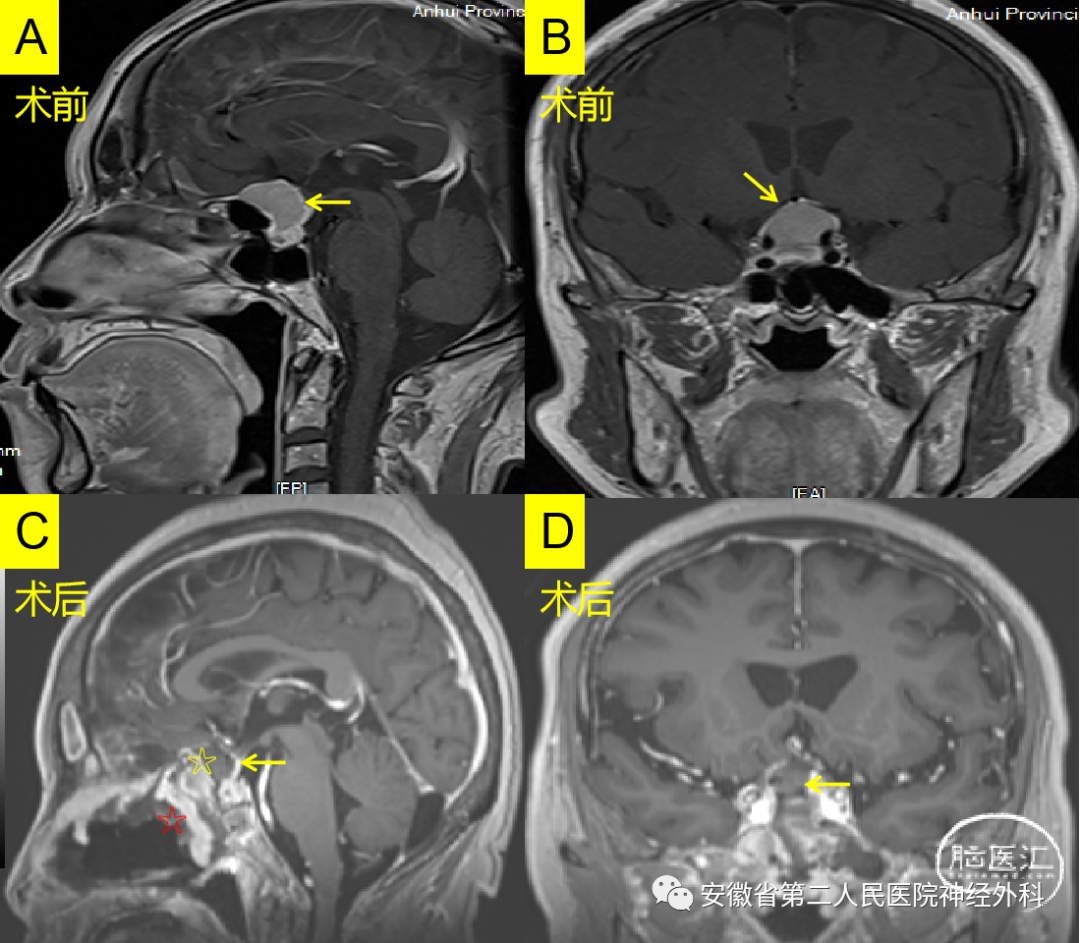

上图:A.术前矢状位增强MRI ,B.术前冠状位增强MRI,C.术后矢状位增强MRI, D.术后冠状位增强MRI。

上图:A.术前矢状位增强MRI ,B.术前冠状位增强MRI,C.术后矢状位增强MRI, D.术后冠状位增强MRI。(☆带蒂黏膜瓣,☆阔筋膜)